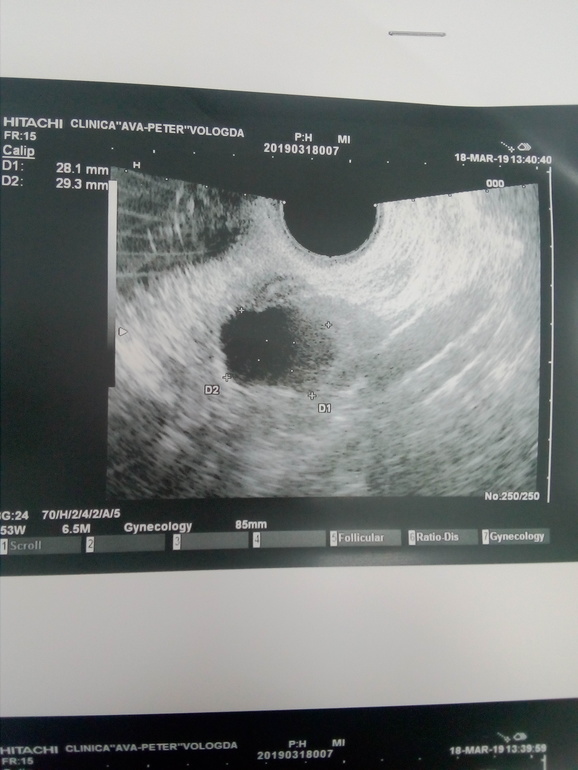

Девушки подскажите может кто то понимает в узи. Что это за киста??? Врач конечно сказала но вот что то у меня сомнения.

больше похоже на кисту ЖТ с прошлого цикла

Диагноз: киста яичника? Может жёлтое тело, края не ровные? Меня репродуктолог в центре планирования беременности на УЗИ супернавороченном смотрела. Увидела что то и говорит, что это фоликул, а это жёлтое тело оказалось, совсем одно и то же🙄🤔

Врач сказала фолликулярная киста. Это на 8 дц. Вот и меня смутило что оно не ровная киста какая то.

Меня тоже тогда смутило, что то, но у моего "фоликула"форма была овальная и чёткие ровные края🤔 А у вашей кисты, края не чёткие. Сколько мм киста?

29мм киста. врач сказала что видимо с прошлого цикла осталась. у меня была в октябре фолликулярная киста и она ровная такая была, ну посути это ведь фолик только большой. И это у меня цикл со стимуляцией. со 2 по 6 дц пила клостилбегит.